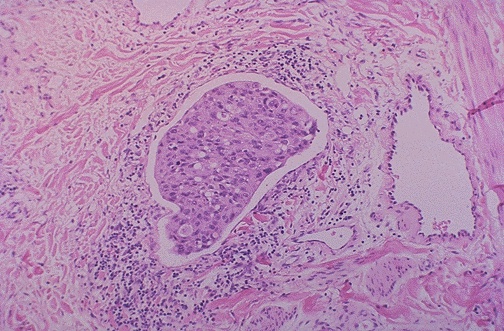

Image 4.4

The high power microscopic appearance of the skin is shown here.